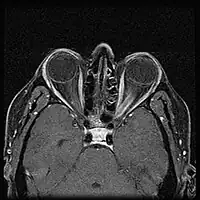

Optic nerve sheath meningioma

| Optic nerve sheath meningioma - Left eye esotropia and proptosis of left eye | |

When ONSM is suspected, MRI of the brain or orbits should be performed. This will usually show characteristic findings and confirm the diagnosis.[5]